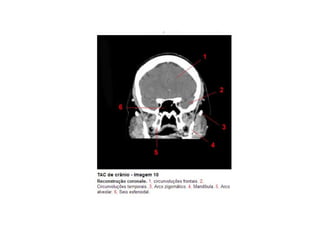

Anatomia E Protocolo Tomografia Computadorizada de Crânio PPT